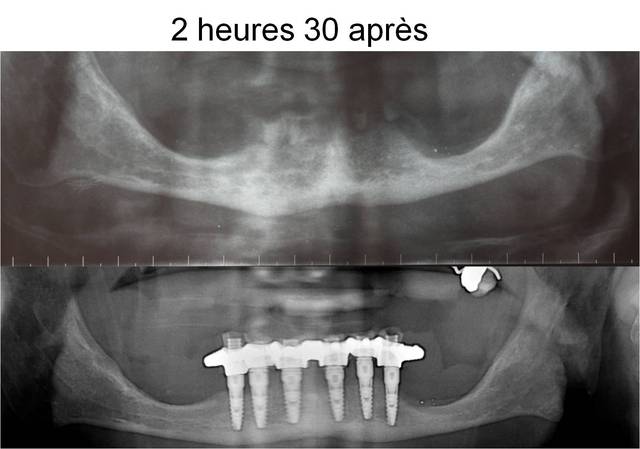

pour une mandibule

2h30 dtnqhc - Eugenol

au maxillaire